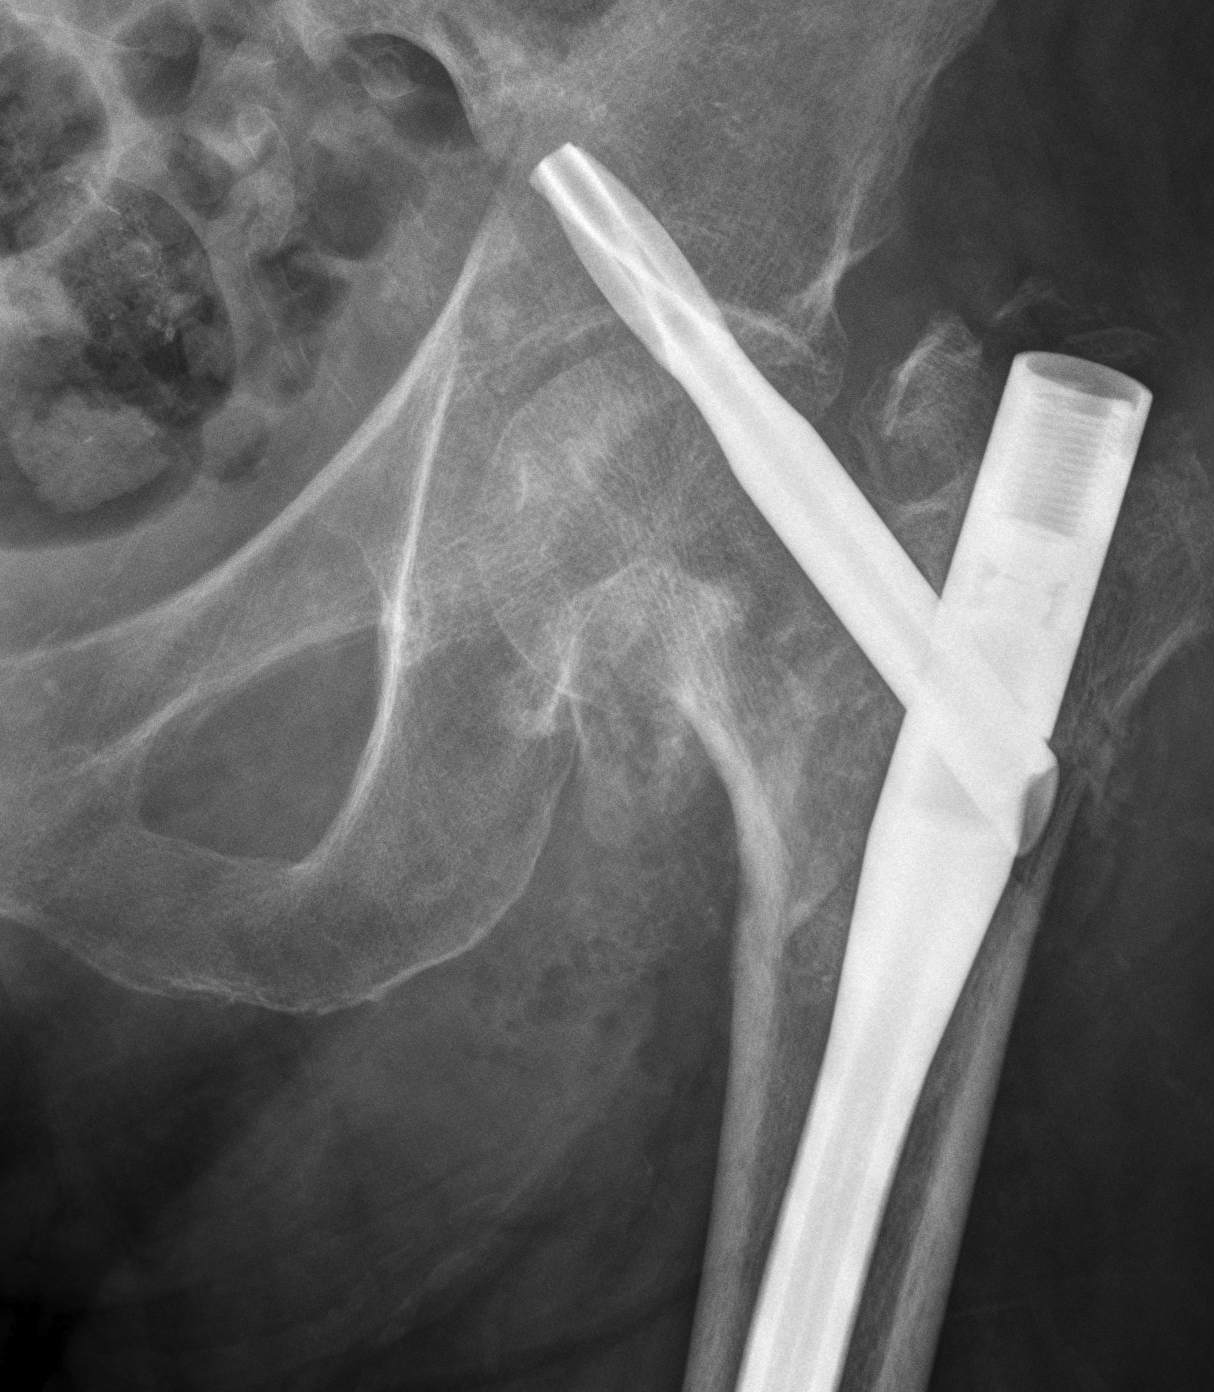

Evans Classification

Two main types

- Type 1 Intertrochanteric

- Type 2 Reverse Oblique

Type 1 Intertrochanteric

2 part undisplaced

2 part displaced

3 part without posterolateral support (GT fracture)

3 part without posteromedial support (LT fracture)

4 part without posterolateral or posteromedial support

Type II Reverse Oblique Type

Inherently unstable - tendency of femoral shaft fragment to shift medially

Reverse oblique fractures

Stability

Depends on medial cortical reduction

Unstable (AO 31.A2 + 31.A3)

- intact lateral wall

- posteromedial cortical fracture

- reverse oblique

- subtrochanteric extension